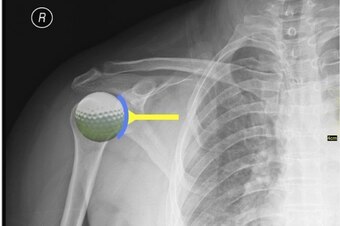

For a better picture, imagine a golf ball sitting on a tee. The golf ball represents the head of the humerus, and the tee represents the shoulder socket. A shoulder labrum widens and deepens the tee's surface, thereby making it more difficult to knock off the golf ball.